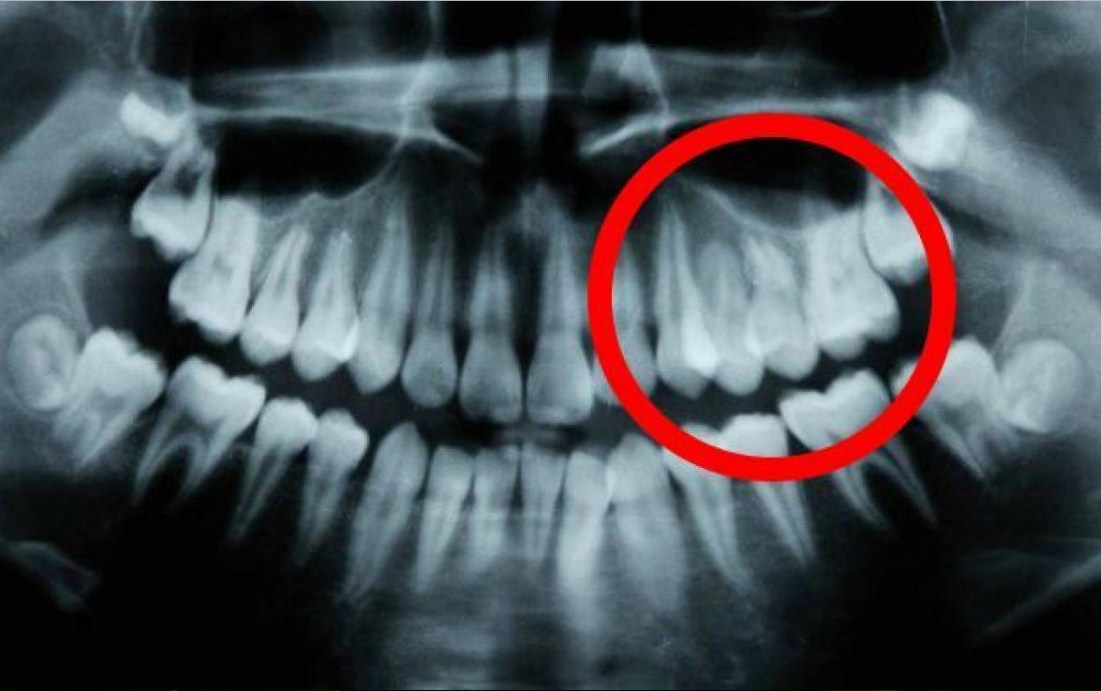

Это обычная вещь, которая продолжается десятилетиями – проблемы с зубами, которые требуют вмешательства стоматолога для устранения кариеса или еще более дорогостоящего и трудоемкого лечения корневого канала.

До сих пор считалось, что если зубы начинают портиться, то вы их либо теряете либо спасаете только через стоматологическую процедуру или полностью удаляете, поэтому это может быть настоящий прорыв в стоматологии.

Из того, что исследователи смогли определить, что эмаль зубов начала восстанавливаться у лабораторных крыс, которым давали лекарство во время первоначальных исследований, относящихся к болезни Альцгеймера, и теперь проводится больше исследований, связанных с восстановлением зубов в целом.

Также было определено, что Tideglusib может восстанавливать только тонкий слой эмали.